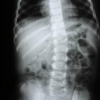

Türkiye'deki 750 Bin Kişiye "Skolyoz" Uyarısı

Sinir Sistem Cerrahisi Derneği Başkanı Prof. Dr. Yücesoy: "Omurga eğriliği adını verdiğimiz skolyozun görülme sıklığı yüzde 1 2 düzeyindedir.

EFSUN YILMAZ - Sinir Sistem Cerrahisi Derneği Başkanı Prof. Dr. Kemal Yücesoy, halk arasında omurga eğriliği adı verilen skolyozun görülme sıklığının yüzde 1-2 olduğunu, yıllarca ihmal edilen, fark edilmeyen ama ağrılara neden olan bu rahatsızlığın erken tedaviyle önlenebileceğini söyledi. Prof. Dr. Yücesoy, AA muhabirine yaptığı açıklamada, skolyozun iki tipinin olduğunu, bunlardan birinin doğumsal ve anne karnındaki gelişim sırasında omurga ile ilgili yaşanan sıkıntıdan kaynaklandığını belirtti. "İdiopatik Adelösan Skolyoz" adı verilen ikinci grubun ise yüzde 90 oranda kızlarda görüldüğünü ifade eden Yücesoy, nedenini tam olarak bilemedikleri bükülmenin ergenliğe geçiş döneminde ortaya çıktığını kaydetti. Eğriliğin erken dönemde fark edilmesi durumunda fizik tedavi, korse gibi yöntemlerle düzeltilebileceğini anlatan Yücesoy, yüzde 20 eğrilik döneminde bükülmeyi izlediklerini, yüzde 20 ve 45 eğrilik düzeyinde fizik tedavi, egzersiz ve korse uygulamaları önerdiklerini, eğim arttıkça ameliyatı tercih ettiklerini ifade etti. -"İhmal edilen hastalar var" Skolyozun toplumda rastlanma sıklığının yüzde 1-2 arasında değiştiğine işaret eden Kemal Yücesoy, "Skolyozda sadece o kemiğin çıkarılması ve altının ve üstünün birbirine bağlanması sonra meydana gelebilecek daha büyük rahatsızlıkları önlüyor.40-45 derece gibi ileri boyutta eğrilik olduğunda ise bunu rijit sistemlerle, vidalarla ve ona bağlı çubuklarla düzeltiyoruz" diye konuştu. Fark edilmeyen, ihmal edilen çok hasta olduğunu dile getiren Prof. Dr. Yücesoy, gerekli önlem alınmadığı takdirde hastanın ilerleyen yaşlarda bel ağrısı veya fıtık şikayetiyle doktora başvurduğunu, bir röntgen filmiyle de altta yatan nedenin "skolyoz" olarak belirlendiğini bildirdi. Fizik tedavi, korse ya cerrahi müdahale ile çözülmeyen sorunun gelecekte bel, bacak, fıtık, siyatik ağrılarına neden olabileceğini vurgulayan Yücesoy, ailelerin çocukların sırtına bakarak kolaylıkla bükülmeyi tespit edebileceğini hatırlattı. Kemik küreklerinin eşit olmasına dikkat edilmesini öneren Prof. Dr. Yücesoy, "İki kemik küreğinin birbirine eşit olmaması, birinin kabarık birinin çökük olması, pantolon giydiklerinde kemerde eğrilik oluşmasa, memelerdeki asimetrik büyüme gibi basit tespitler önemli" dedi. Skolyozun özellikle genç kızlarda güzellikle ilgili bir problem de yarattığını aktaran Yücesoy, sırta giyilen kıyafetlerin eğri durduğunu, vücudun üst bölümünün eğrildiğini, hatta boyun da kısaldığına işaret etti. Yücesoy, ameliyat sonrası özellikle çocuk hastaların aynı gün ayağa kalktığını ve gündelik yaşamına geri döndüğünü sözlerine ekledi. - İzmir